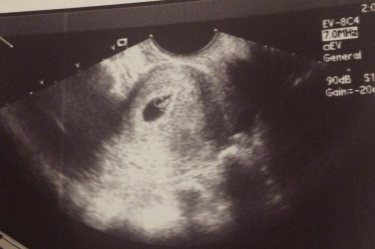

Календарь беременности

ура❤️❤️❤️❤️